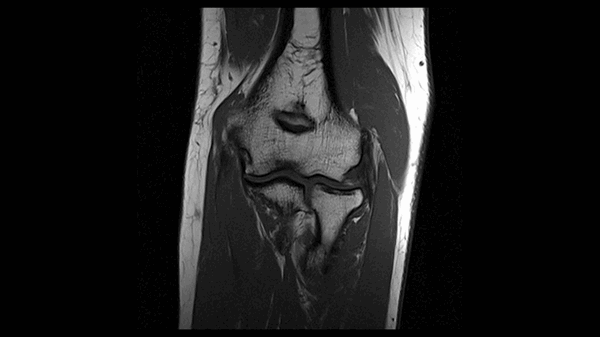

б)МРТ локтевого сустава в корональной плоскости. Общее сухожилие разгибателей в месте прикрепления к латеральному надмыщелку плечевой кости неравномерно утолщено, МР-сигнал от него неоднородно повышен на PD FS-ВИ и Т2-ВИ за счет выраженного отека и разволокнения (признаки латерального эпикондилита), общая целость его не нарушена. Окружающие мягкие ткани с признаками отека.